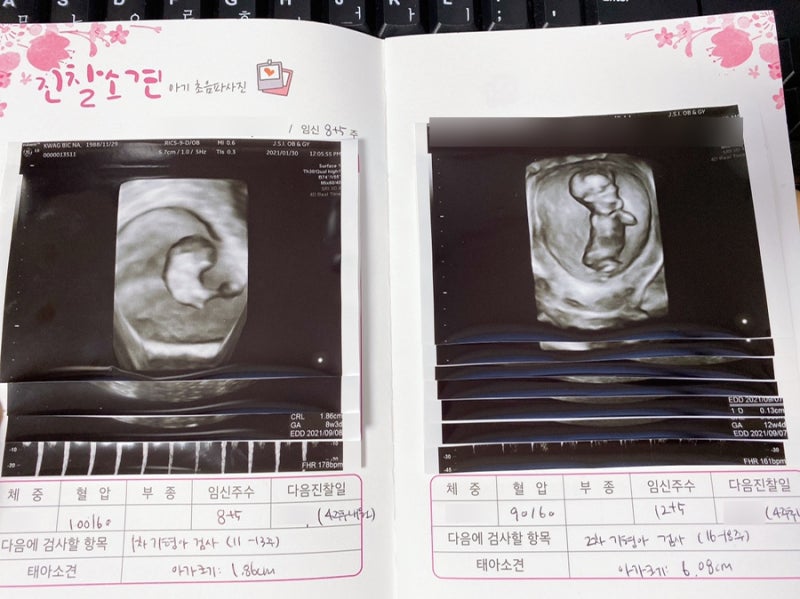

# 2차 기형검사 준비

구체적인 주수는 사람마다 다르지만 대부분 15~16주에 2차 기형검사를 받고 결과가 나오기까지 1주일이 걸린다. .